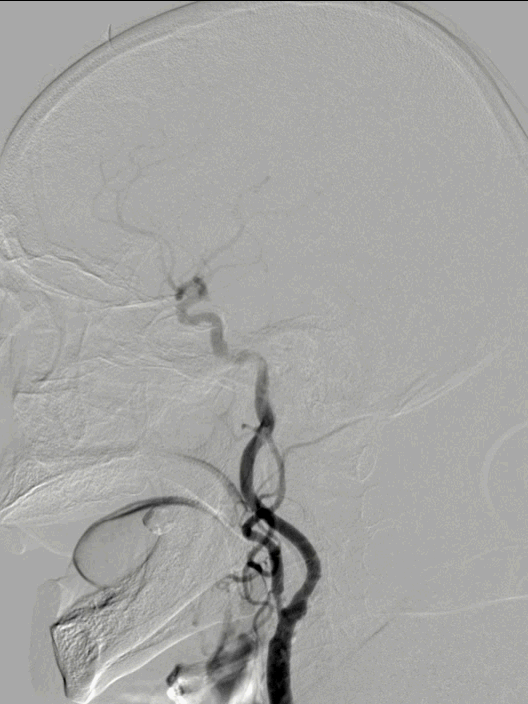

脑血管造影:3型主动脉弓,右侧颈内动脉起始段闭塞,后循环及左侧颈内动脉均未向左侧颈内动脉供血区代偿。

3型主动脉弓,用Mani管超选至右颈总动脉,用260cm加硬泥鳅导丝交换出,在泥鳅导丝导引下,用125cm的多功能管将6F Infinity长鞘置于右颈总动脉,提供稳定支撑。

在Synchro2微导丝及微导管引导下,Catalyst7抽吸导管顺利到达颈内动脉末端。

Catalyst 7抽出大量负荷血栓,大脑中动脉上干仍未显影。

微导丝微导管超选至大脑中动脉上干,微导管造影确认在血管内真腔内,释放Solitaire 4×20mm。

Solitaire 4×20mm支架锚定Catalyst 7抽吸导管到达M1段,抽吸导管负压,拉出取栓支架,取栓过程中Catalyst 7维持稳定。

两次支架取栓取栓取出血栓,血管再通。